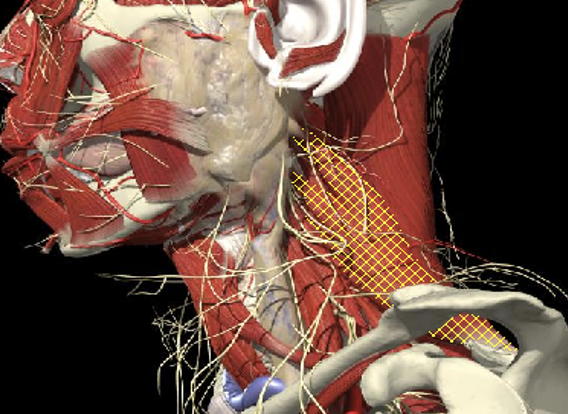

Muscles deep

Not easily identified by surface landmarks

Not palpable on examination

Deep Layers

Splenius Capitis

Splenius Cervicis

Semispinalis Capitis

Semispinalis Cervicis

Layer 1

Layer 2

Layer 3